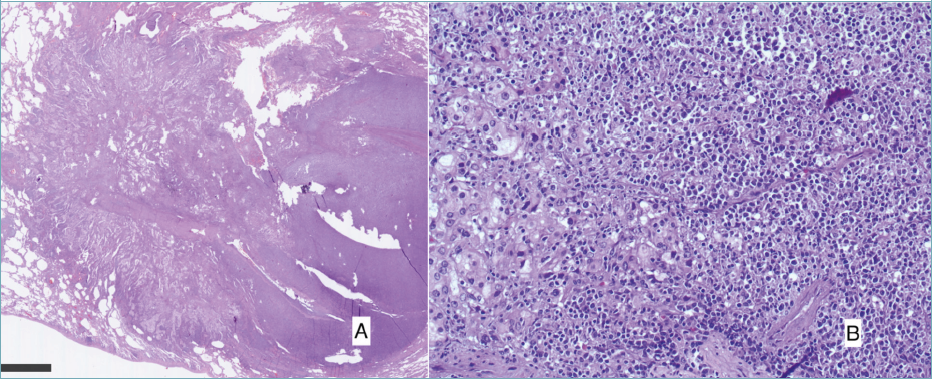

A lung nodule in the right upper lobe was occasionally detected in a 74-year-old man. The nodule had spiculate margins measuring 23 mm x 11 mm with a SUV max 23.3 at PET CT (Fig. 1). Histologically, the trans-bronchial lung biopsy showed a non-small cell carcinoma infiltration with roughly glandular structures, so the diagnosis of adenocarcinoma was made and the lung primitivism was demonstrated by the TTF1 positivity (Fig. 2).

Figure 1. Pre-operative CT scan and 18FDG-PET CT, showing right upper lobe lesion